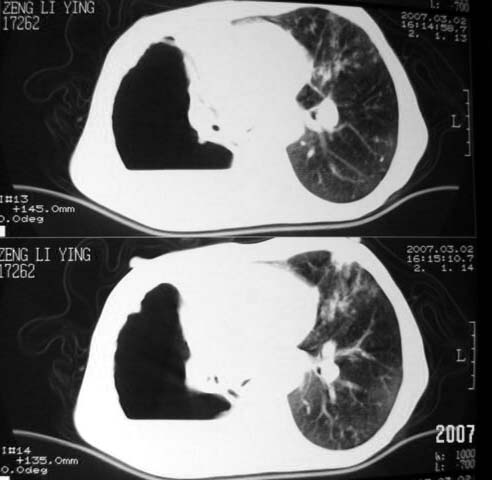

以下是引用dyqct在2007-3-2 22:04:00的发言:[br]考虑:1、右侧毁损肺伴支气管胸膜瘘(多条支气管与胸腔相通、液气胸);[br] 2、左肺浸润型肺结核。[br][br][br][br]